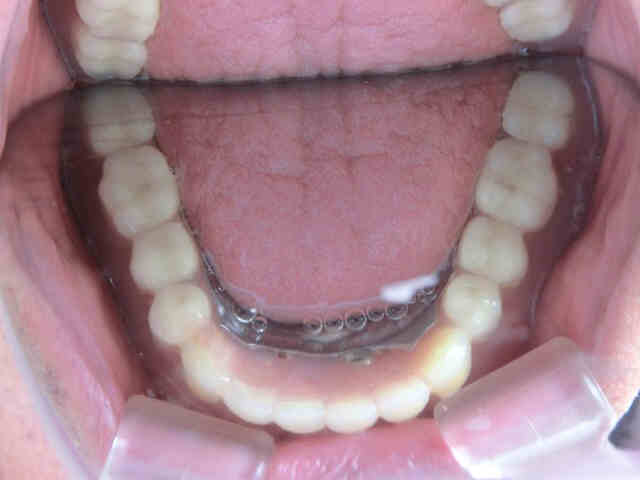

新たに作製した義歯は金属フレームを内蔵した耐久性の高い金属床義歯で、装着時は軽く押し込むだけで装着でき、ピンク色の床部分を持ち上げると簡単に取り外せます。この構造により、インプラント周囲の清掃や義歯の洗浄が容易で、衛生的な管理が可能です。